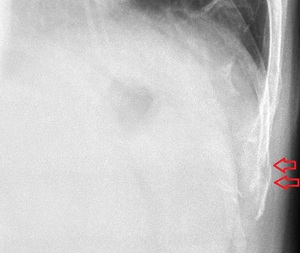

川越市男性 肋骨の痛み 肋骨骨折

左第10肋骨 超音波長軸像 左同部 レントゲン画像

川越市60代男性、会社員。 肋骨の痛み、肋骨骨折。

【原因】

原因は、思い当たるとしたら自家用車の運転席のアームレストに患部が当たっている時に、後部座席にある

荷物を手を伸ばして取ったことくらいしか思いつかないそうです。 しかし、その時には激痛は感じなかったが、

2,3日経過と共に体を捻るような体勢によって痛みが出現してきました。

当接骨院にて超音波観察を行ったところ、左第10肋骨体部で2か所に骨折が認められました。(左上画像矢印。)

精査依頼先クリニックのレントゲン撮影においても骨折が認められました。(右上画像矢印。) この患者さんは、

転倒したり硬い物が患部にあたった訳でもなかったので、骨折だったことに驚いておられました。